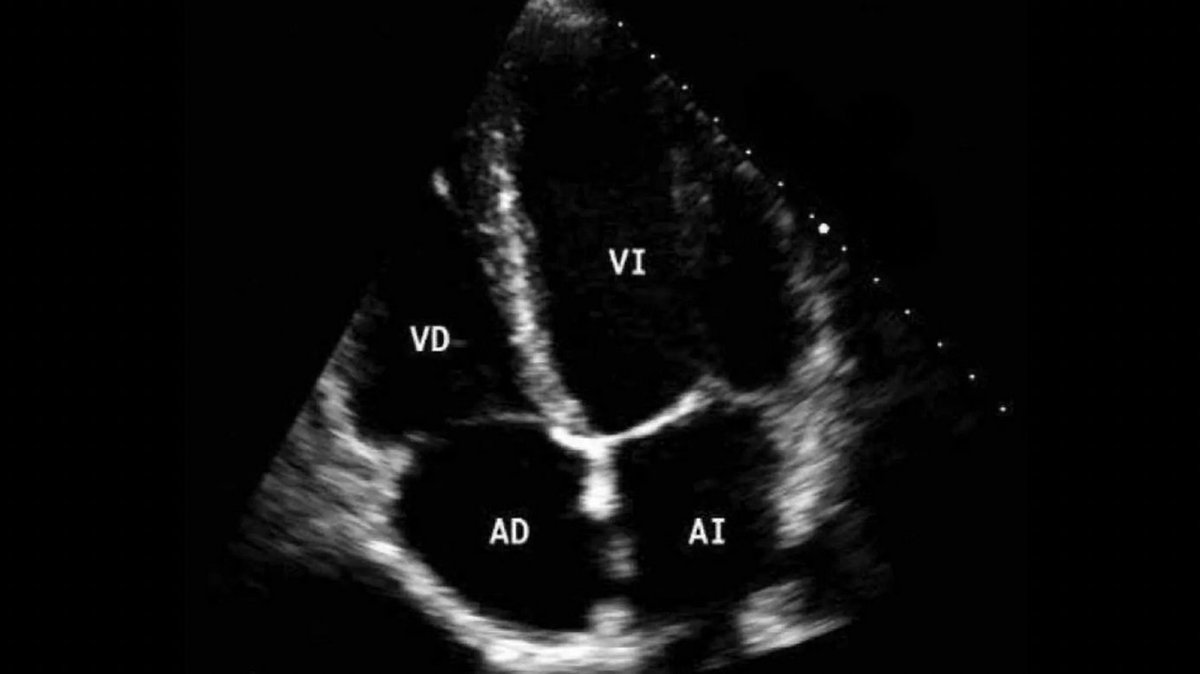

I ed. del curso de #Ecocardioscopia, una técnica inocua y de bajo costo que permite un estudio muy preciso y rápido de las patologías cardíacas 🗓️Miércoles 19 de febrero 🏥Hospital Clínico San Carlos 🧑🏫Alberto de Agustin Eduardo Pozo #imagenCardíaca fundacionfic.es/evento/ecocard…